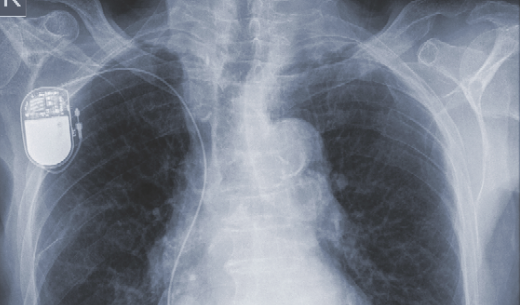

Aman Chugh, MD; Preeti N. Malani, MD; Yasser Rodriguez, MD, MBA; Frank Davis, BS

Implantable cardioverter-defibrillators (ICDs) are small, battery-powdered electrical impulse devices that can be implanted in patients at-risk for sudden cardiac death due to ventricular tachycardia and...